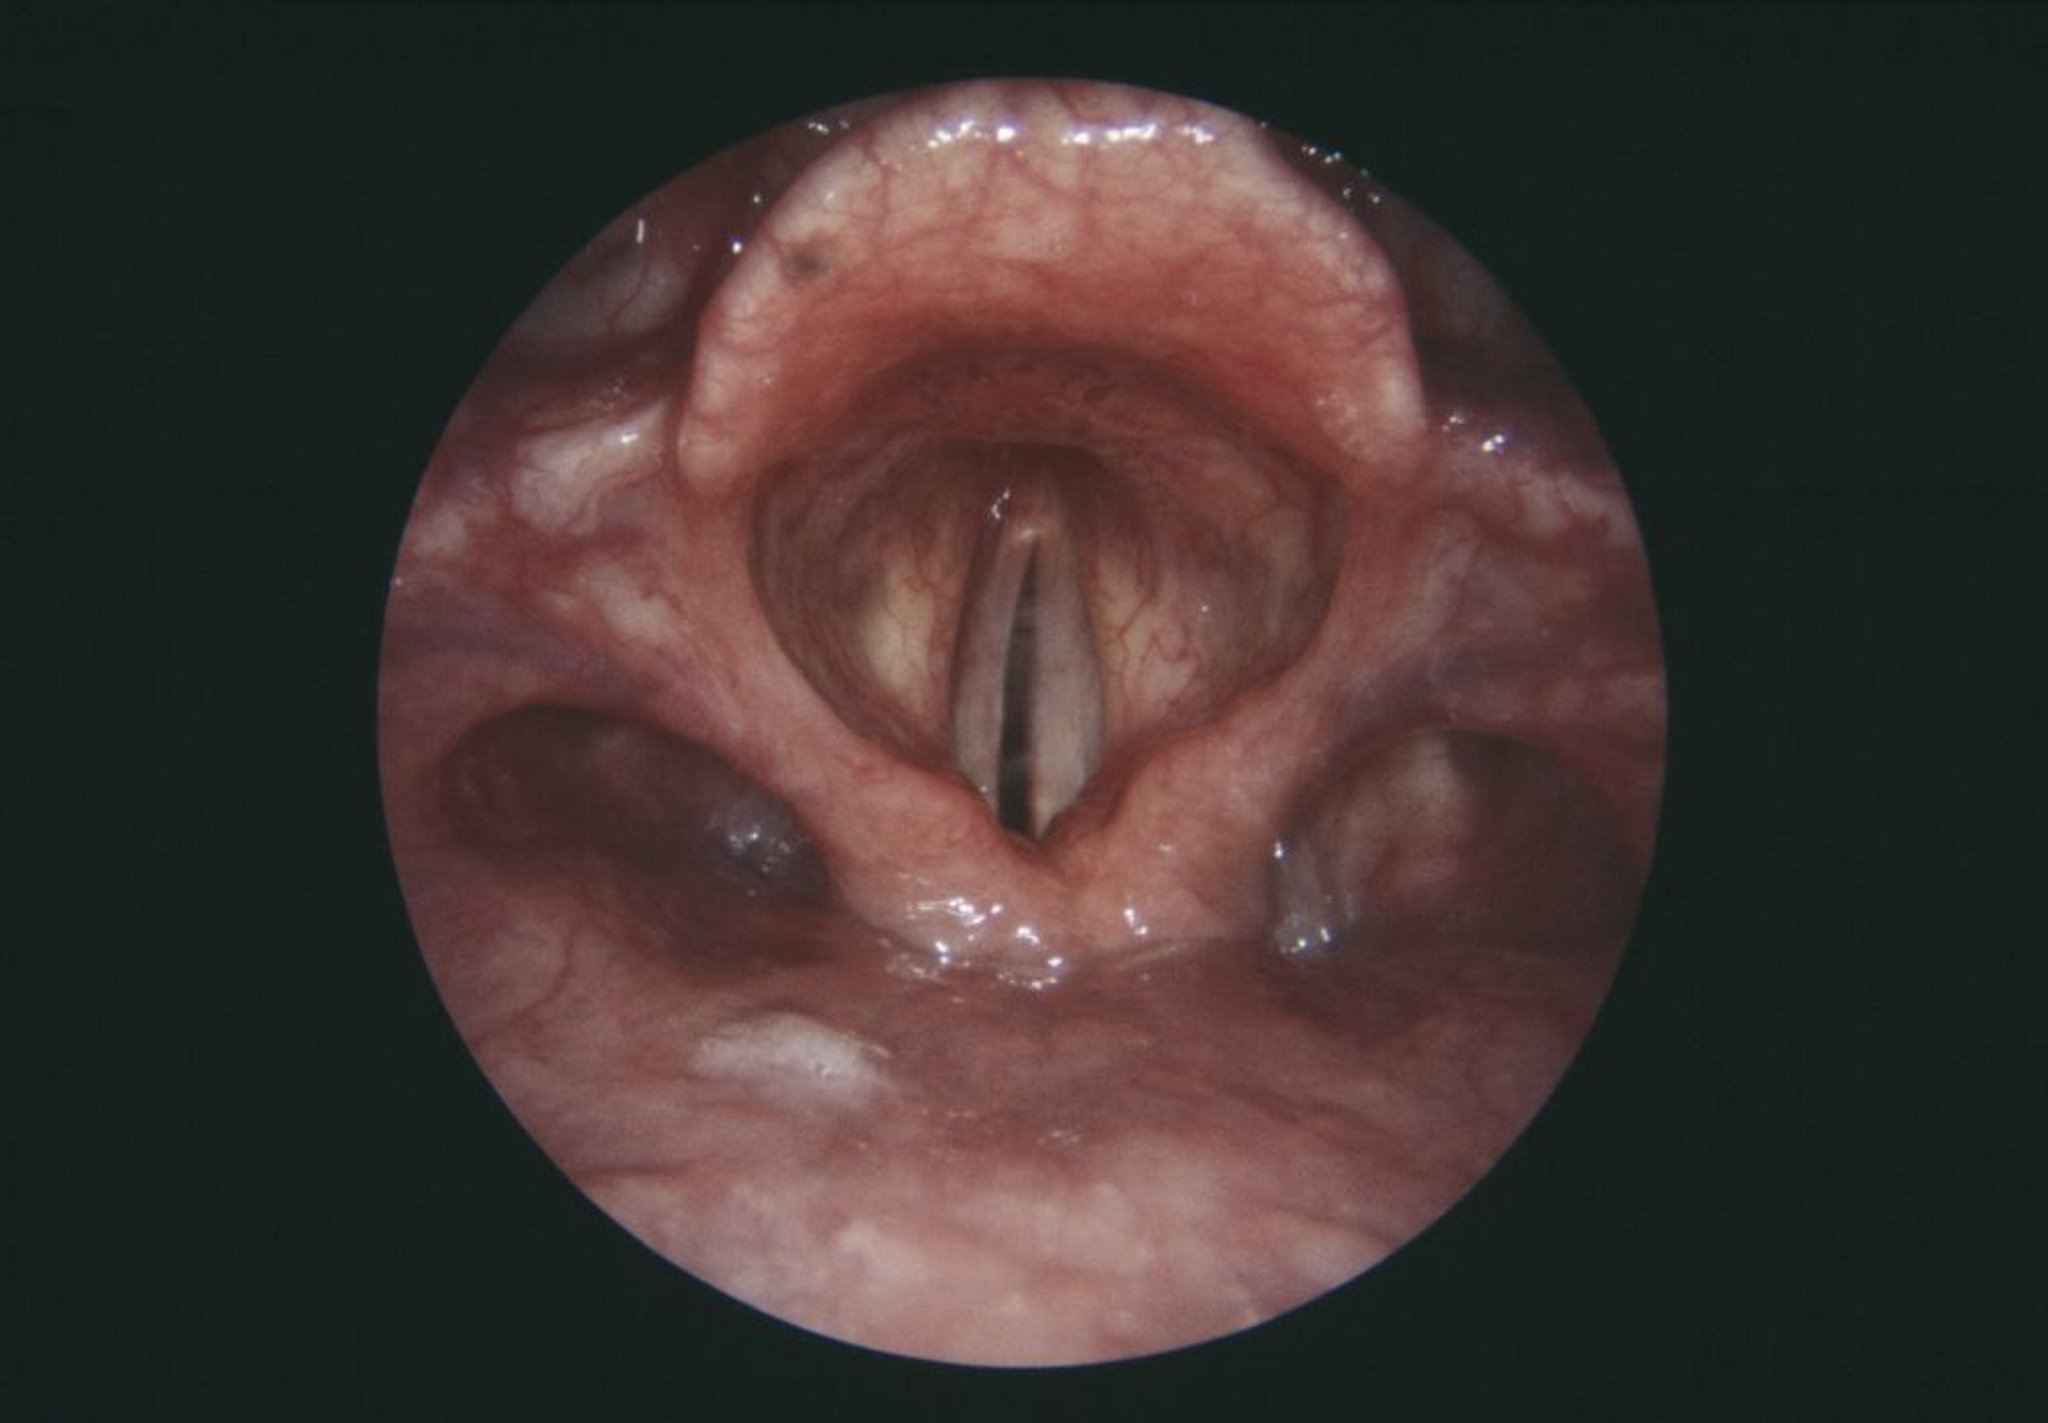

声帯麻痺

この喉頭の内視鏡像には,麻痺した右側の声帯(灰色,中央左)が写っている。